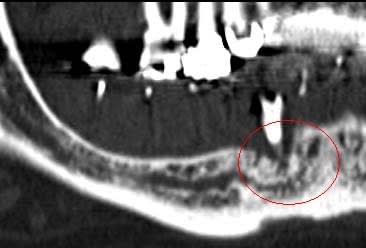

Je mets les coupes scan et tu comprendras son hésitation

Le prochain cas je propose volontiers d'être assisté par qui le veux bien, apprendre est mon plaisir, et je ne suis pas aussi buté en vrai que dans les discussions